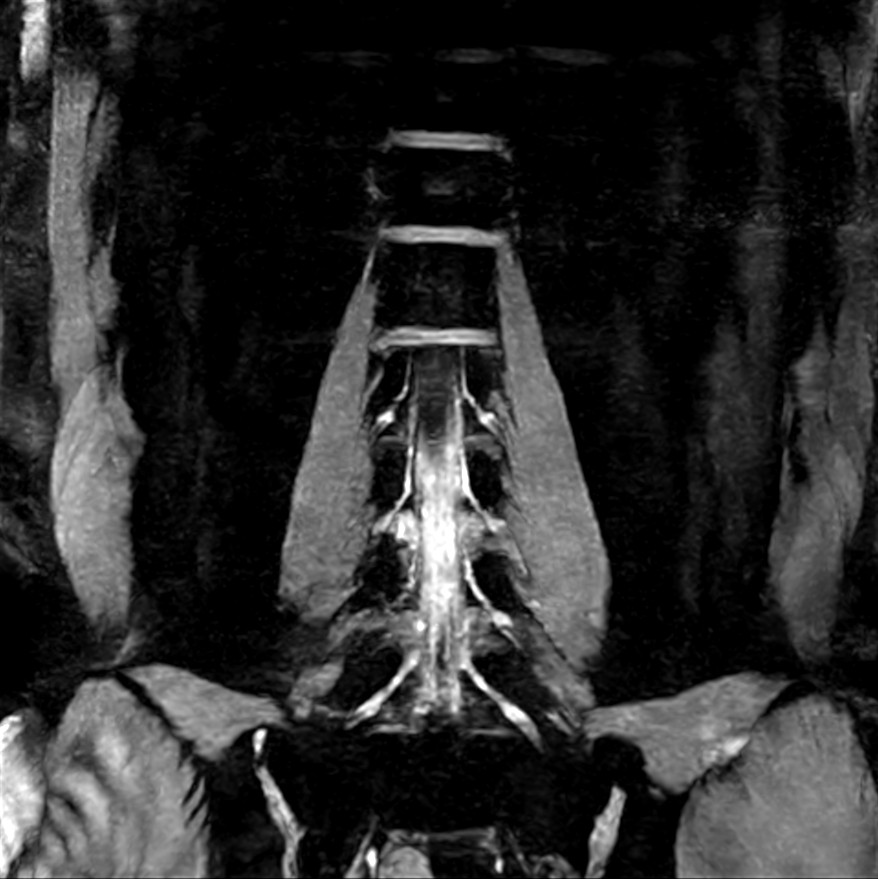

Coronal 3D WATS